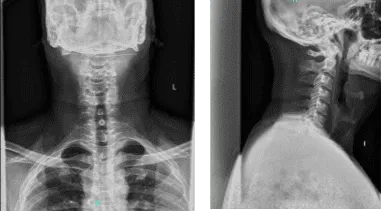

Presentó los resultados de la radiografía del hombro derecho que mostraron artropatía de la articulación acromioclavicular. En la cadera izquierda, las radiografías han mostrado una leve sobrecobertura acetabular. Para la columna cervical, reducción leve del espacio discológico.

Radiografía: 2 o 3 vistas de la columna cervical